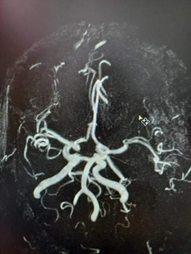

When studying 120 MR-angiograms of individuals without disorders of cerebral circulation we have found the typical anatomy of Willis circle in 32% of cases only (Figure 1). In other 68% of patients from this group, the different variations were found, namely: hypoplasia/aplasia of the anterior communicating artery was noted in 23% (Figure 2), aplasia or hypoplasia of one of the posterior communicating artery in 21% of cases, 17% of patients showed the combination of both anterior and one of the posterior communicating arteries, aplasia of the anterior and both posterior communicating arteries were noted in 4% of cases, the parietal contact of both anterior cerebral arteries were found in 3%.

Figure 1 Typical circle of Willis.